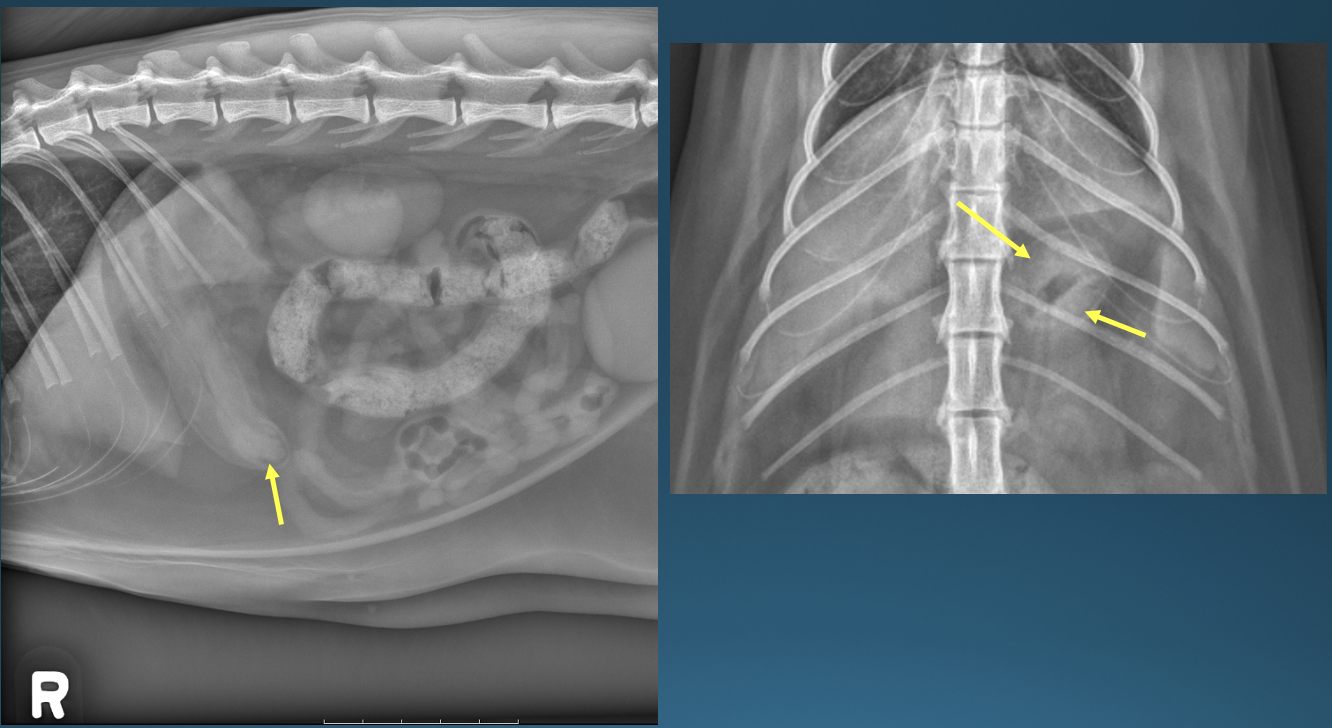

What is shown in these images?

A

left: normal canine stomach

right: normal feline stomach